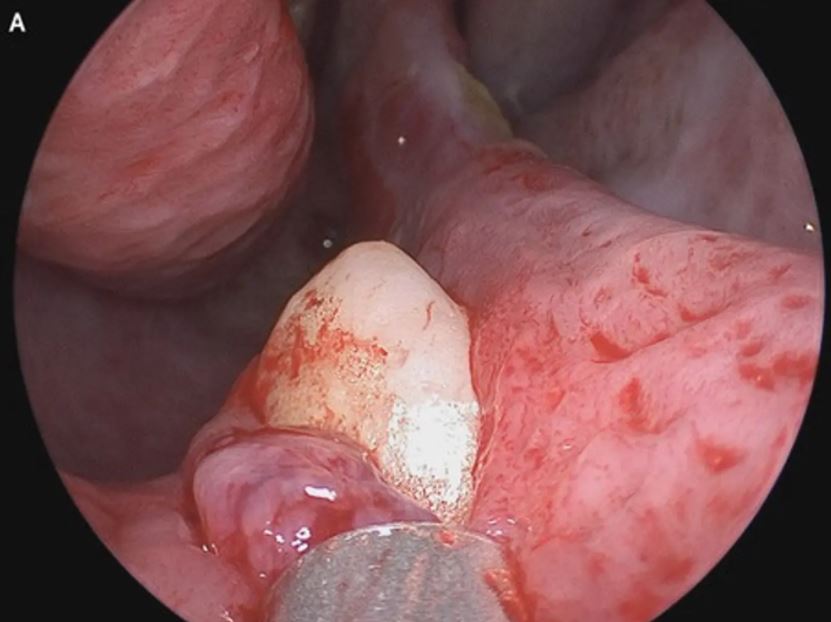

Doktor yang menjalankan pemeriksaan seterusnya mengesan jisim putih yang keras pada lubang hidung sebelah kanan, dan disahkan batang gigi ektopik terbalik.

Kes yang jarang berlaku ini mendapat perhatian ramai dan akhirnya berjaya diselesaikan dengan melakukan pembedahan kecil.